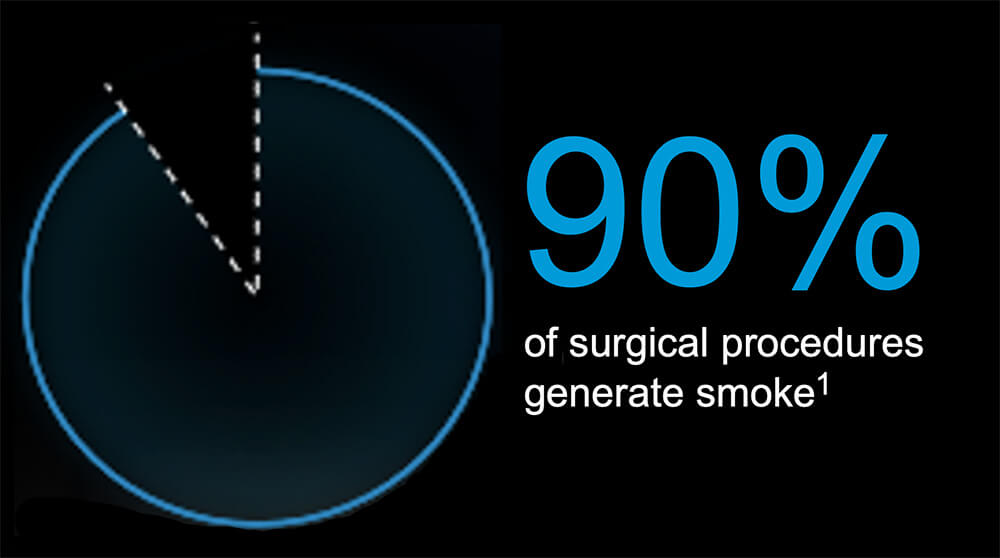

1Steege AL, Boiano JM, Sweeney MH. Secondhand smoke in the operating room? Precautionary practices lacking for surgical smoke. Am J Ind Med. 2016;59(11):1020-1031.